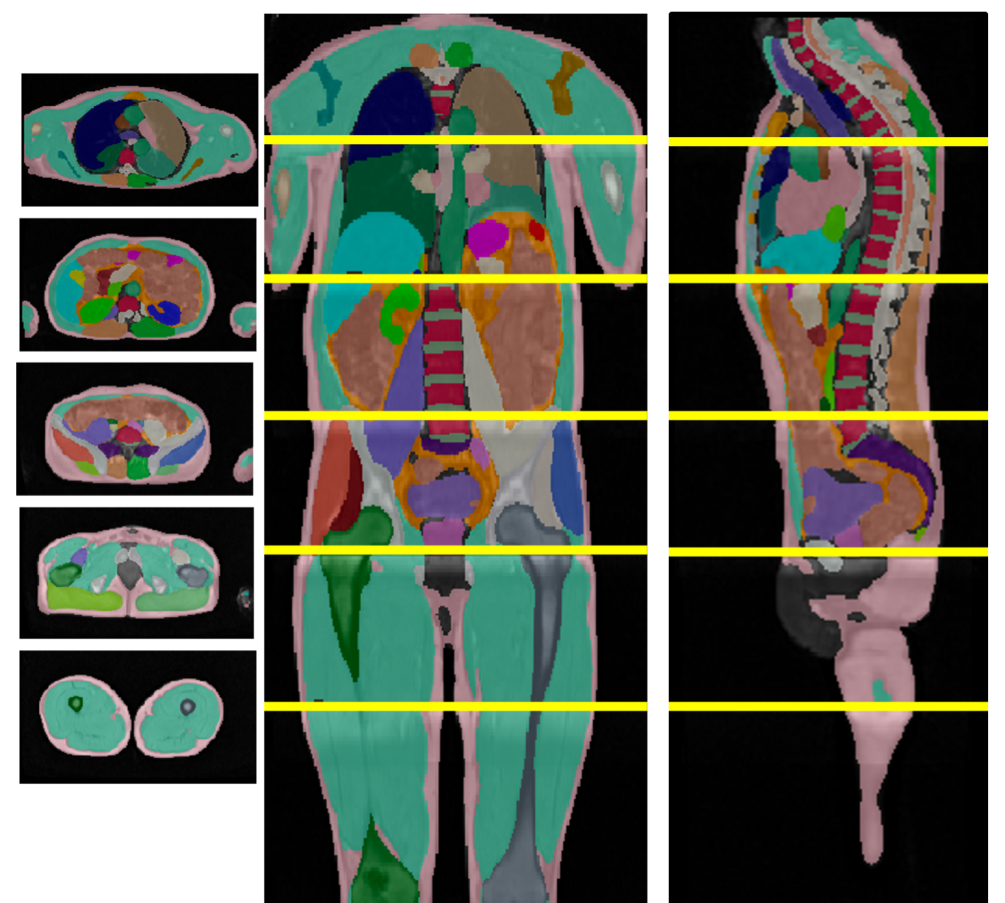

![[Uncaptioned image]](x1.png)

\captionof

figureUKBOB Size and Diversity. Our proposed UK Biobank Organs and Bones (UKBOB) is the largest labeled medical imaging dataset for segmentation, comprising body organs of 51,761 MRI 3D samples (17.9 M 2D images) and a total of more than 1.37 billion 2D masks of 72 organs. Left: we show label examples from UKBOB from axial, coronal, and sagittal views. Right: We show a plot of the size (number of 2D images) and diversity (number of classes) of our UKBOB compared to other medical images datasets. The size of the bubbles indicates 2D image resolution. This new scale in dataset size and diversity should unlock a new wave of applications and methods in the computer vision and medical imaging communities.